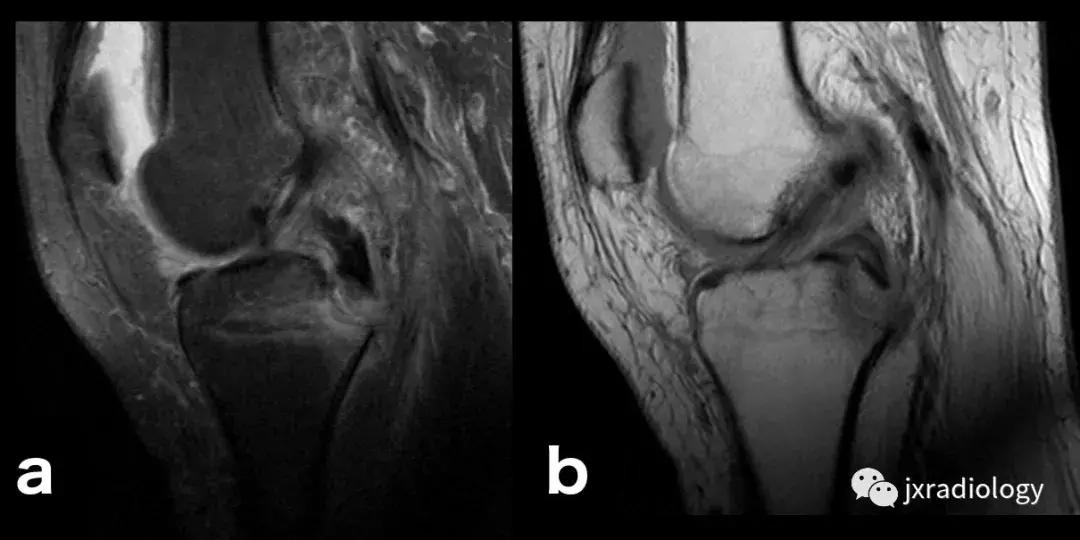

图4:SIF(软骨下不全性骨折):在过去,每当在股骨内侧髁上观察到这种软骨下病变时,它就被标记为膝关节自发性骨坏死(SONK)。 现在它被认为是一个不全性骨折。这些不全性骨折通常发生在股骨内侧髁和股骨头,并存在于老年人中(它们与骨质疏松症和生物力学改变相关,如在不稳定的半月板损伤中。 与其他应力性骨折类似,低信号的骨折线在水敏性序列(a,b:冠状和矢状PDWI-FS)上被高信号的骨髓水肿包围。

图5:长期的SIF(软骨下不全性骨折)伴股骨外侧髁软骨下塌陷、大面积水肿(不如上图中显示的内侧髁位置常见)。

图6:内侧胫骨平台上不常见的SIF(软骨下不全性骨折)(a,b:矢状和冠状PDWI-FS)。